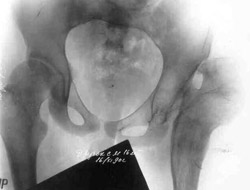

Congenital dislocation of left hip.